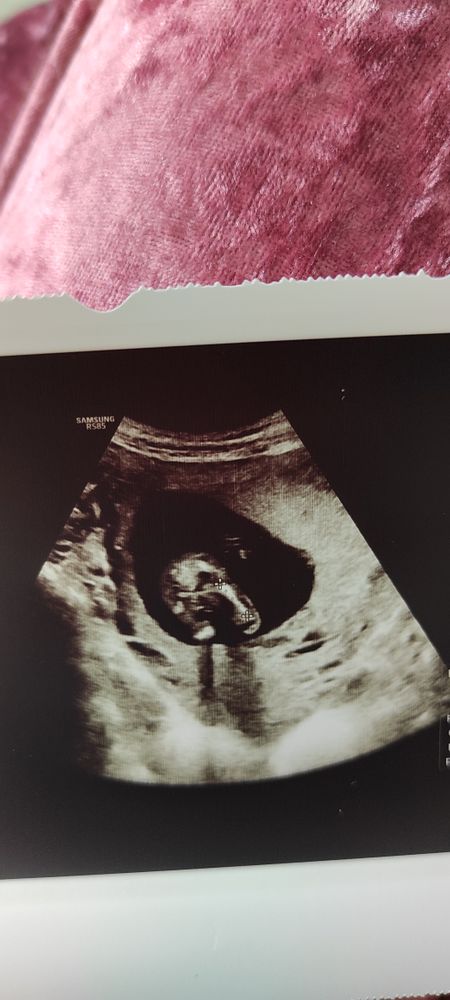

Какой пол малыша?

Конечно может все поменяться, на 14 неделе там бугорок половой, а не органы)

Очень на мальчика похоже, но лучше переделайте узи через 2 недели

Точно мальчик

Фото неудачное , вроде что-то видно, а вроде и нет 🤔